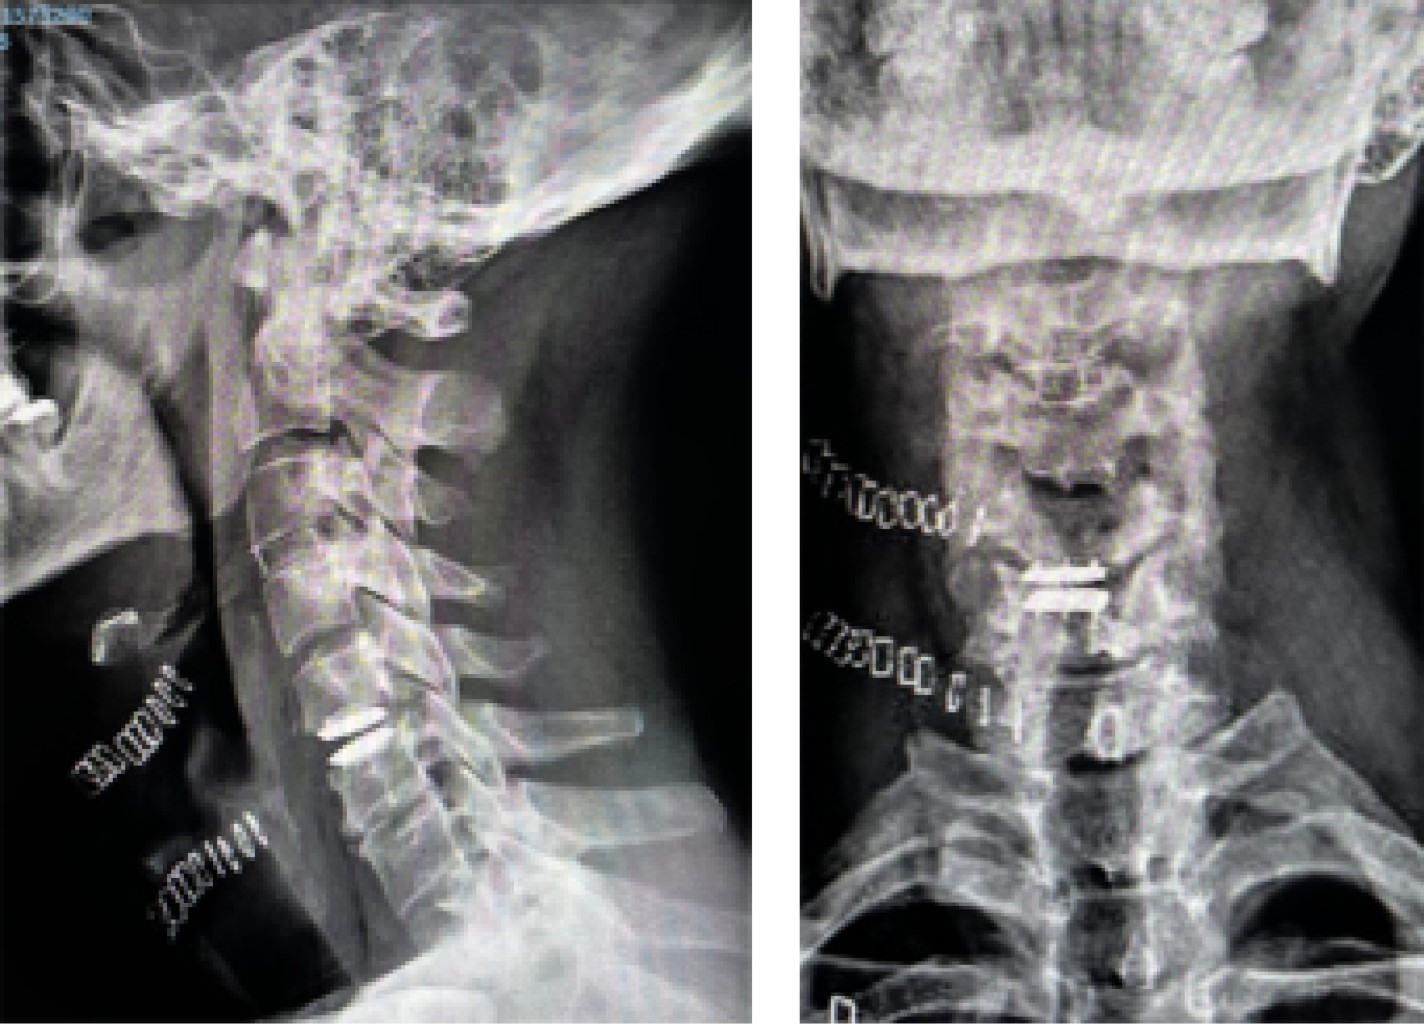

Figure 1